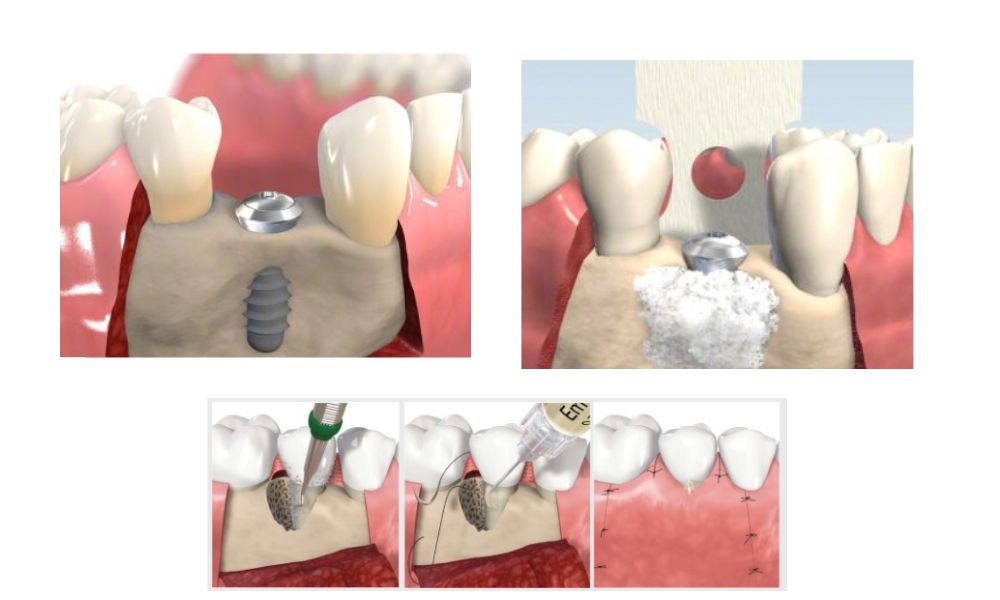

A külső arcüreg emelés során a szakorvos a felső állcsont oldalsó felén egy ún. csont ablakot nyit, és ezen keresztül emeli meg az arcüreg nyálkahártyáját, majd juttatja be a csontpótló anyagot.

- Helyi érzéstelenítés után lebenyt képez, és egy csontablakot képez, amin keresztül elérhető az arcüreg nyálkahártyája

- Megemeli az arcüreg nyálkahártyáját, majd az így létrejött térbe csontpótló anyagot helyez. Ezzel erősíti meg a csontszerkezetet vagy növeli a csontállományt, lehetővé téve az implantátumok biztonságos és sikeres beültetését.

- A csontablakot a csontpótló tetejére visszahelyezi, vagy membránt használ és titán szegecsekkel rögzíti a csontozathoz, melynek feladata, hogy a csontpótló anyagot rögzítse a regenerálódási időszak során.

- Varratokkal zárja a műtéti területet.

A gyógyulási időszak alatt a csontpótló anyag fokozatosan integrálódik a meglévő csontszövetbe. Amennyiben a beavatkozás nem az implantátum behelyezésével egyidőben történik, a csont megerősödését követően nyílik lehetőség az implantátumok beültetésére.